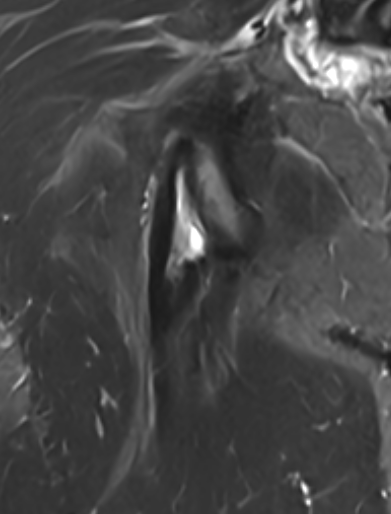

High grade partial tear proximal hamstring

High grade partial tear proximal hamstring